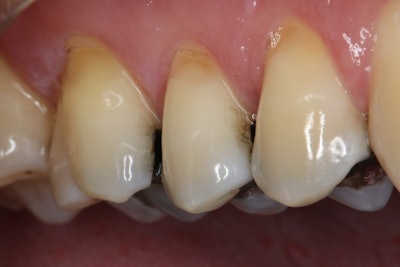

Figure 6.

The treatment met the patient's expectations (Figure 6), alleviating discomfort during chewing and eliminating cold sensitivity, enabling the patient to enjoy cold foods and beverages without discomfort. Since completing the treatment, the patient's oral health has improved. The man was referred for a sleep study evaluation to address bruxism, and adjacent teeth are being restored as needed. Regular hygiene visits were recommended to the patient for maintenance and monitoring.